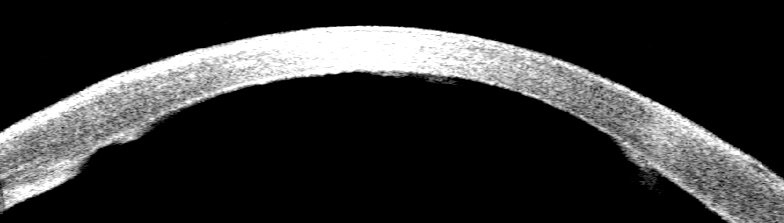

術(shù)后,李先生的角膜內(nèi)皮很好地進行了貼附,角膜變透明,角膜厚度也隨之下降(見圖),終于不用再經(jīng)受眼痛的折磨了。

【OCT顯示:術(shù)前角膜增厚,大泡】

【術(shù)后OCT顯示:角膜內(nèi)皮植片薄,貼附良好,角膜厚度下降】